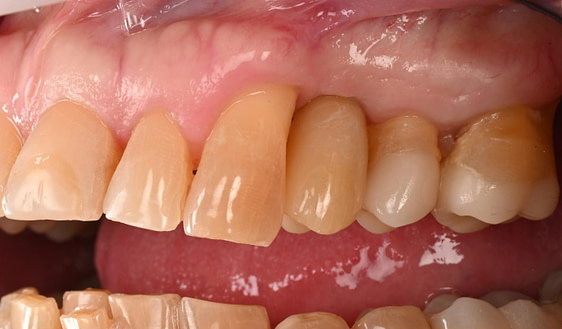

Three months after the implant surgery, a thorough post-operative assessment revealed excellent healing and implant stability.

The crown was milled from a high-strength, multilayered zirconia and hand-finished to achieve a lifelike appearance.

At the final appointment, the crown was securely attached to the implant, resulting in a beautiful, natural-looking restoration.

The successful completion of the implant treatment was evaluated based on aesthetics, function, and patient satisfaction.

The implant-supported crown seamlessly integrated with the patient's natural dentition, and the patient reported excellent comfort and function.

A radiographic assessment confirmed the proper integration and positioning of the implant.